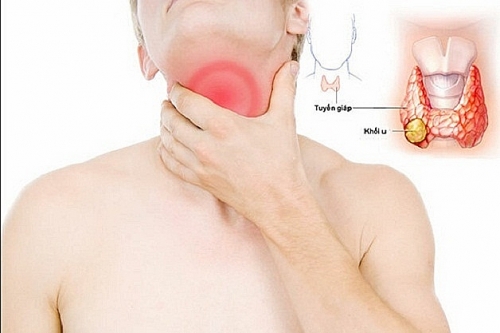

Triệu chứng ung thư tuyến giáp giai đoạn đầu

Những triệu chứng ung thư tuyến giáp giai đoạn đầu là gì và cần làm thế nào để phòng tránh ung thư tuyến giáp?

Triệu chứng u tuyến giáp ác tính

Triệu chứng u tuyến giáp ác tính bao gồm những gì? U tuyến giáp ác tính có thể chữa dứt điểm khỏi bệnh hay không?

Biểu hiện ung thư tuyến giáp

Biểu hiện ung thư tuyến giáp là gì? Ung thư tuyến giáp có nguy hiểm chết người hay không?